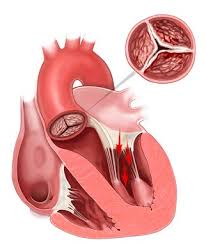

As principais causas de insuficiência mitral são prolapso de valva mitral, doença cardíaca reumática e endocardite. Essa...